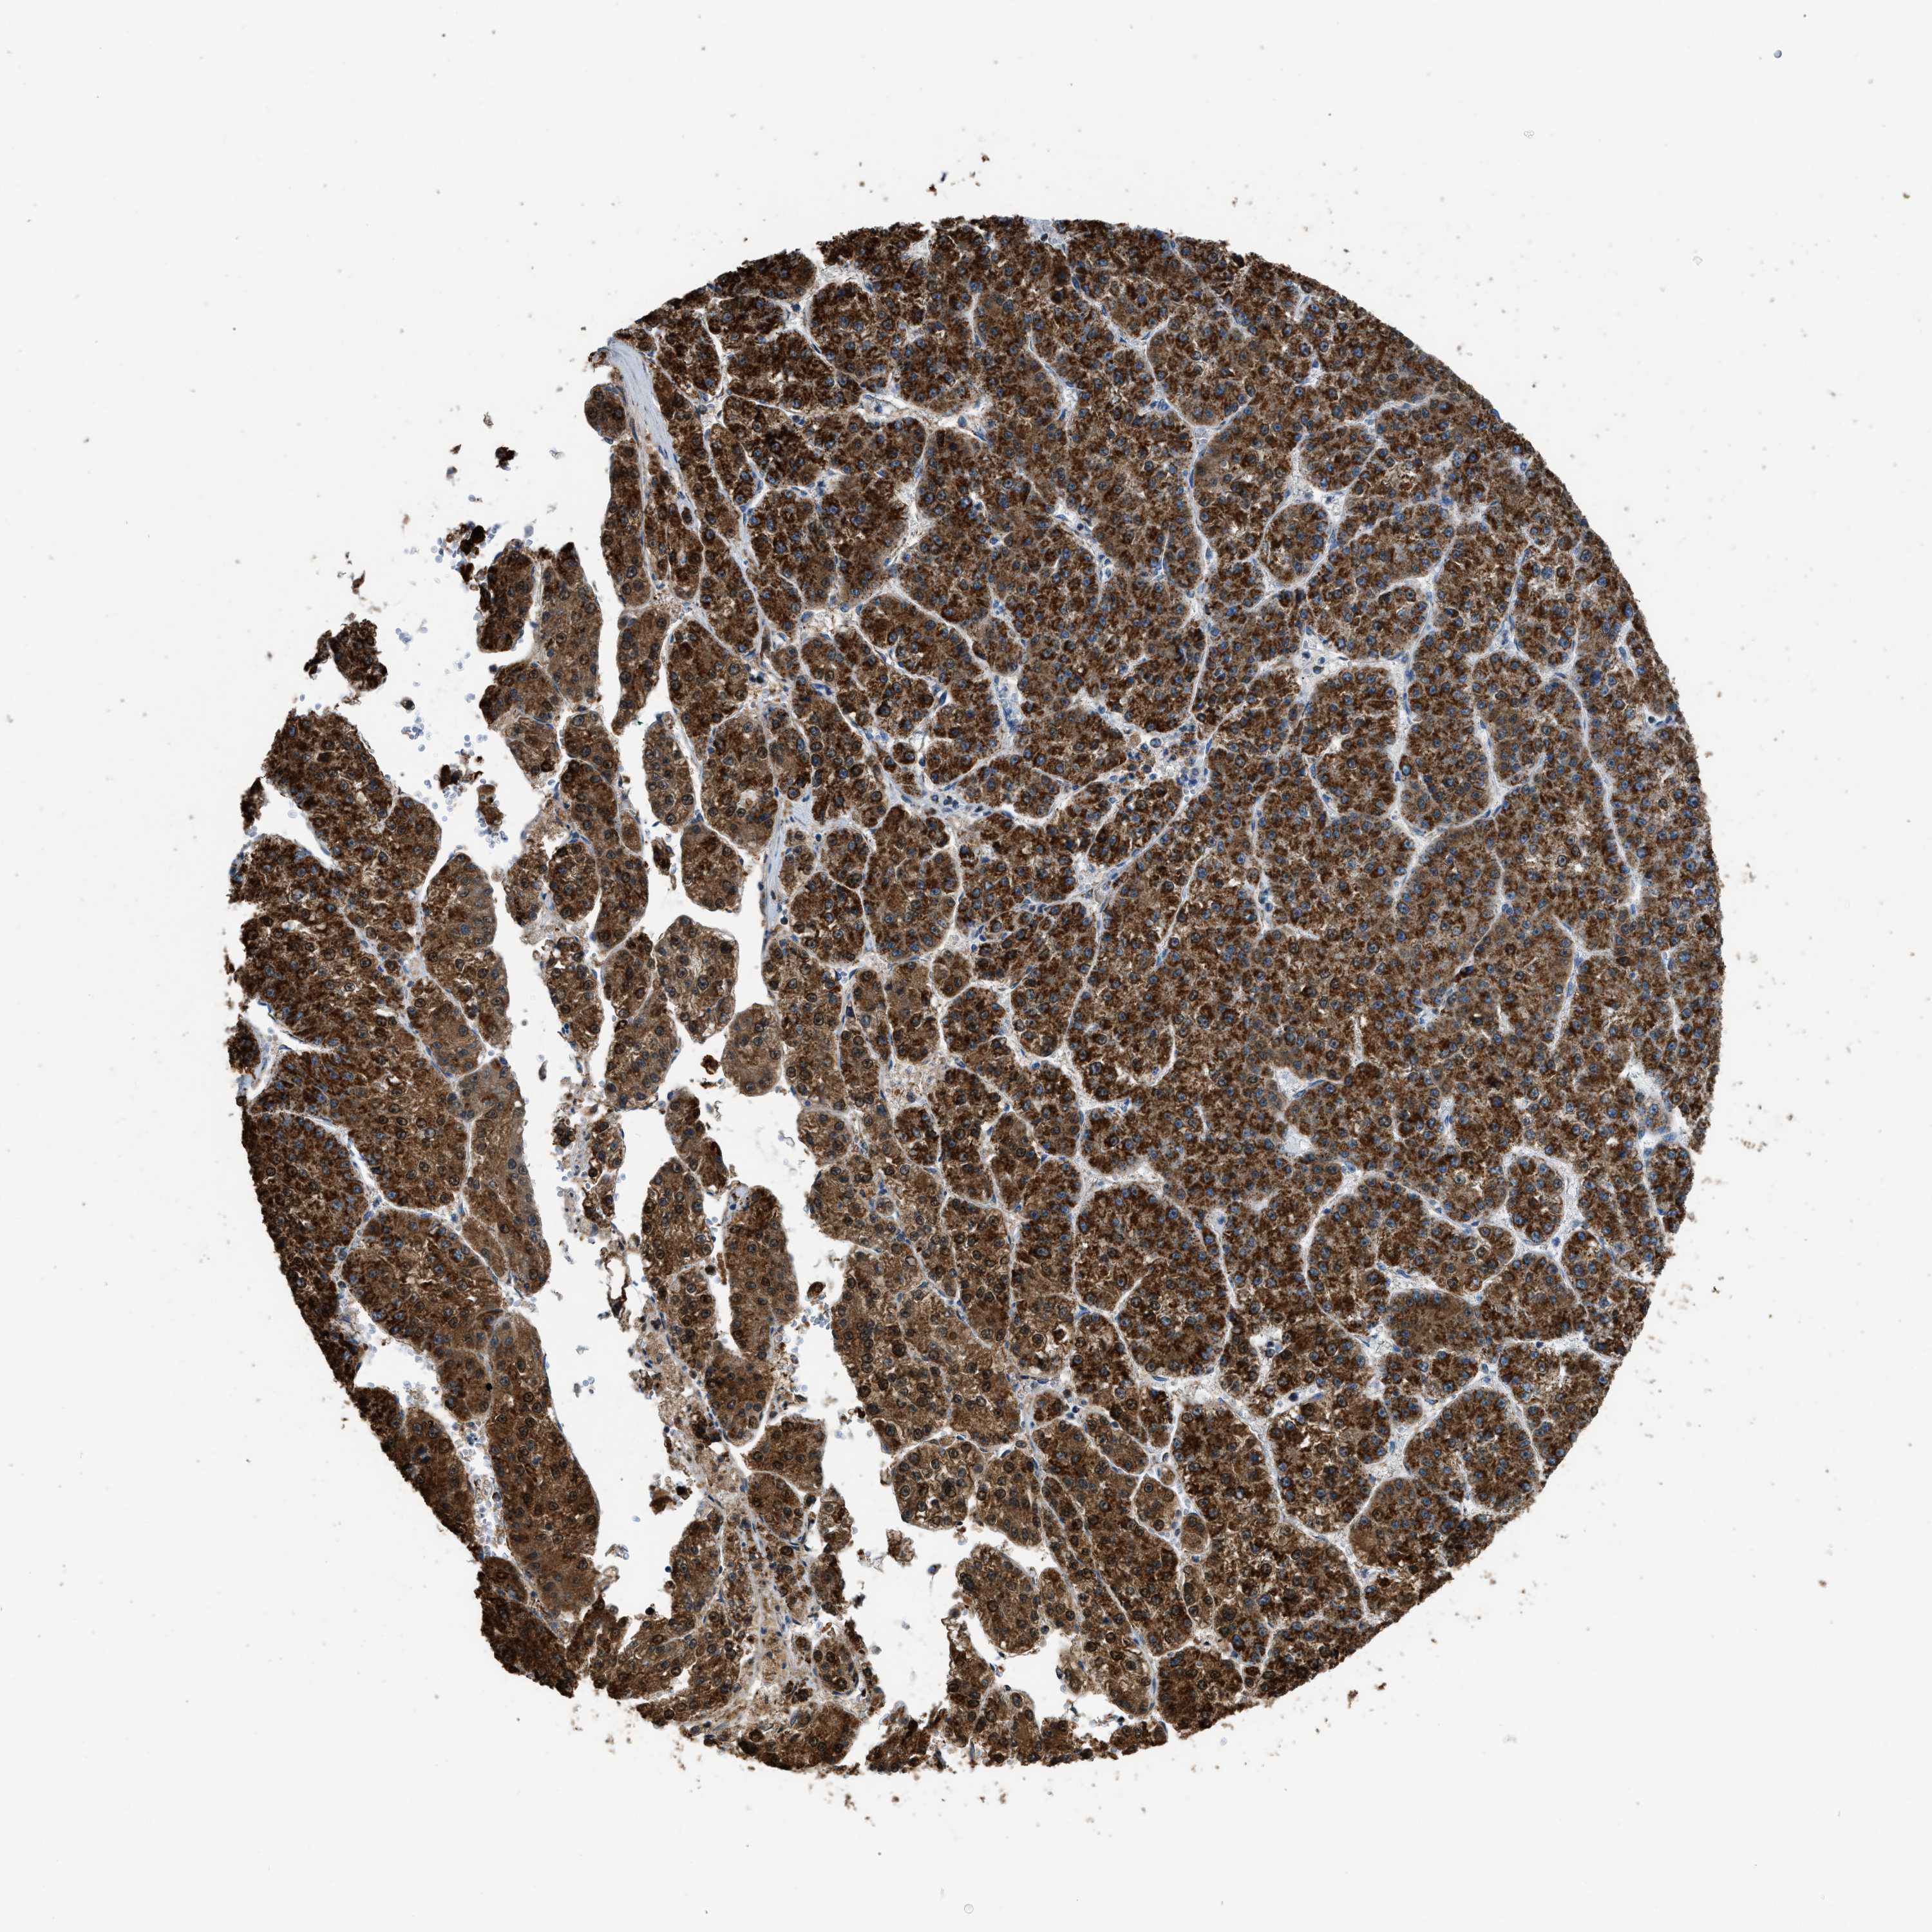

LIVER CANCER - Protein expressioni

A mouse-over function shows sample information and annotation data. Click on an image to view it in a full screen mode. Samples can be filtered based on level of antibody staining by selecting one or several of the following categories: high, medium, low and not detected. The assay and annotation is described here.

Note that samples used for immunohistochemistry by the Human Protein Atlas do not correspond to samples in the TCGA dataset.

Antibody stainingi

Antibody staining in the annotated cell types in the current human tissue is reported as not detected, low, medium, or high, based on conventional immunohistochemistry profiling in selected tissues. This score is based on the combination of the staining intensity and fraction of stained cells.

Each image is clickable and will lead to virtual microscopy that enables deeper exploration of all samples and also displays staining intensity scores, fraction scores and subcellular localization as well as patient and tissue information for each sample.

Antibody HPA018910

Antibody HPA018921

Antibody HPA018923

Staining

High

Medium

Low

Not detected

Intensity

Strong

Moderate

Weak

Negative

Quantity

>75%

75%-25%

<25%

None

Location

Nuclear

Cytoplasmic/membranous

Cytoplasmic/membranous,nuclear

Cholangiocarcinoma

Carcinoma, Hepatocellular, NOS